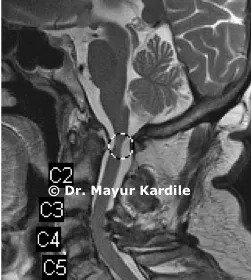

A 61-year-old gentleman with rheumatoid arthritis complaining of neck pain and gait instability. He also had clumsiness of hand movement and spasticity.

Investigations revealed instability between the first and second cervical vertebra causing dynamic compression of the cervical spinal cord.

C1 - C2 stabilization and fusion were done using C1 lateral mass and C2 translaminar screw fixation. Postoperative CT scan and X-ray show good C1 - C2 reduction.